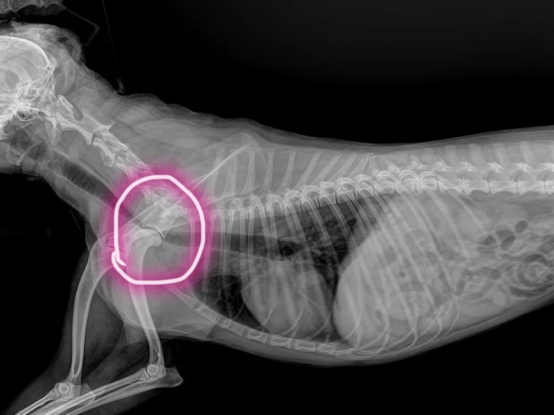

2.气管塌陷:在小型犬中较为常见,如吉娃娃、约克夏、贵宾犬等。咳嗽症状类似“鹅鸣音”,也比较像打喷嚏的倒吸气声,在运动后、兴奋时或受到外界刺激(如冷空气、烟雾)时,症状会更加明显。

(犬气管塌陷影像学检查)